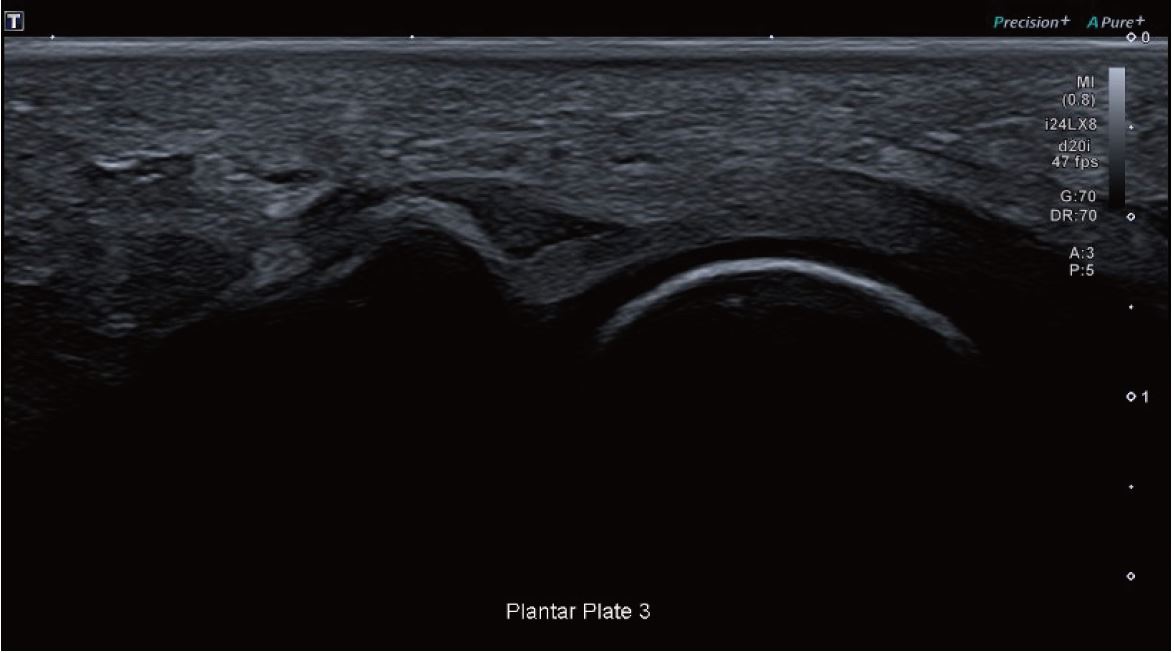

Зображення 3 Розрив третьої плантарної пластини.